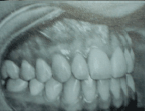

Relacione a coluna da direita com a da esquerda, conforme os problemas encontrados nas fotografias intraorais e depois marque a sequência correta.

(1) Retrator muito pequeno

(2) Fotografia tomada abaixo do plano oclusal

(3) Retrator muito grande e muito visível

(4) Fotografia não tomada para o lado suficiente

(5) Fotografia tomada acima do plano oclusal